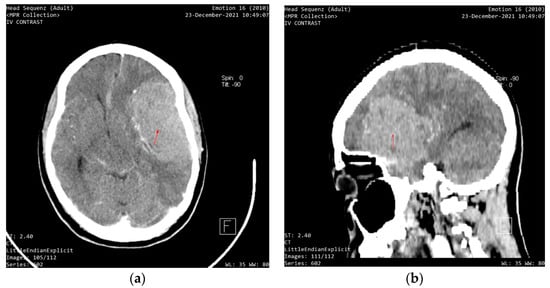

Entry VA was 6/12 in the right eye and hand motion in the left eye. The pupillary responses were sluggish. Intraocular pressure was 13 mmHg in the right eye and 20 mmHg in the left eye, with no improvement in VA with pin-hole. Fundoscopy revealed a bilateral 0.4 cup-to-disc ratio with pallor. She was using timolol eyedrops in both eyes for ocular hypertension (intraocular pressure before therapy was 24 mmHg in both eyes, and previous visual fields and nerve fiber analysis were normal). There was arteriolar attenuation in both eyes, with macula hemorrhages in the left eye. A C-shaped halo was visible in the left eye. An initial assessment of unilateral papilledema with contralateral optic nerve atrophy was made due to intracranial hypertension. The patient was referred for a same-day computerized tomography (CT) scan, which showed an intracranial mass (Figure 2). This patient was immediately sent for a specialist consult at the neurosurgery department of the federal state teaching hospital. She was scheduled for emergency brain surgery immediately after the consult. The lady later passed away due to complications of the lesion and surgery.

Figure 2. (a) An axial section showing a contrast image depicting a well-circumscribed, homogenous mass compressing the left frontal lobe; (b) A sagittal section shows a contrast image depicting an intracranial mass.